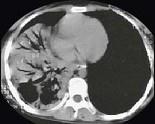

问题 女,24岁,咳嗽咳痰伴高热3天,如图所示,最可能的诊断为 ( )

选项 A.右下肺干酪性肺炎 B.右下肺大叶性肺炎 C.右中肺大叶性肺炎 D.右中叶肺脓肿 E.右下肺不张

答案 B